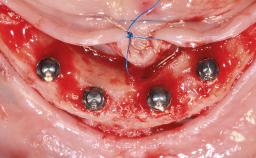

Simultaneous Maxillary and Mandibular Full-Arch Fixed Rehabilitation: Extractions, Immediate Implant Placement and Loading, and Definitive Zirconia Prostheses

An alert and ambulatory 60-year-old male patient presented with a desire to "repair or replace his teeth". A detailed clinical evaluation revealed multiple missing teeth. Generalized severe calculus and biofilm accumulation was noted, associated with poor oral hygiene. All remaining teeth were mobile and showed more than 50% attachment loss. All molars showed furcation involvement. Caries was prevalent throughout the remaining dentition. The patient reported intolerance of his existing removable partial prosthesis, which had been fabricated more than 20 years previously.